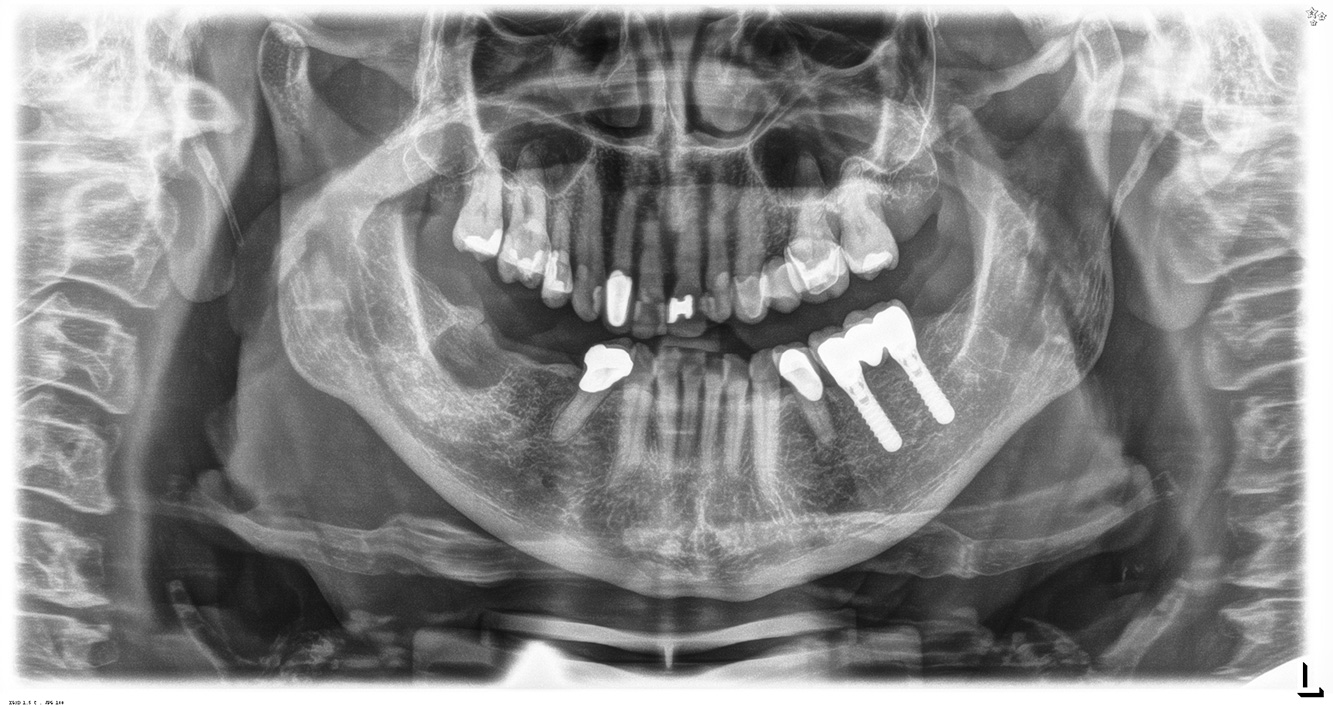

Pacient sănătos cu boală parodontală incipientă

Pacientul în vârstă de 68 de ani nu are nicio afecțiune generală și nu ia niciun medicament care ar putea fi relevant pentru sănătatea sa orală, iar stilul său de viață nu prezintă niciun risc special. Pacientul are două implanturi dentare (cadranul 3, de cinci ani) și un caz anterior de boală parodontală (stadiul IV, gradul B) cu pierderea dinților. În prezent, condițiile parodontale sunt stabile. Cu toate acestea, parodontoza crește semnificativ complicațiile biologice ale implanturilor și există riscul de pierdere a implanturilor (21). Se pot determina patru recomandări pentru ședința de profilaxie. mai multe